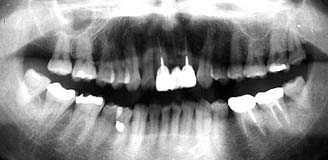

| 初診時 パノラマ | 10年後 パノラマ |

| 年齢の割に歯周疾患進行は軽度 46歳 男性  |

歯槽骨吸収の形跡はほとんど見あたらない |

口腔内およびX線所見:

口腔清掃状態は比較的良好で、カリエスは数カ所存在したがいずれも軽度であった。

また、歯槽骨は全体に軽度な吸収が認められるが、年齢の割には軽度であった。

処置および経過:

主訴である左上7番と右下6番のカリエス治療終了と同時に来院が途絶え、2年間の空白期間の

のち再び来院。再来時、左右下顎の臼歯部の抜髄と補綴処置を行ったのちメインテナンスに移行

した。その後も小規模なカリエスを行ったものの順調に経過して現在に至る。

途中(初診より8年目)、「7は歯根破折により抜歯。

考察:

50歳といえば、そろそろ歯槽膿漏の末期的状態の歯が目立ち始める年齢である。その50歳を挟ん

だ10年間に歯槽骨の吸収がほとんど見あたらないのは比較的稀な出来事といえる。

本症例では、元々歯周疾患進行傾向が低かったことと、継続したメインテナンスが幸いしたもの

と思われる。